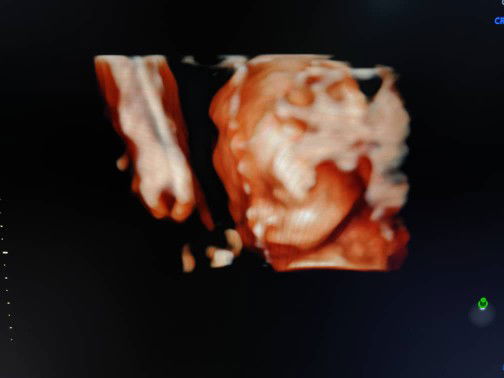

Mommies sekarang dekat trimester yang ke berapa? Alhamdulillah sis 2 more weeks untuk habis 1st trimester ?

33 weeks 2 Day 😅